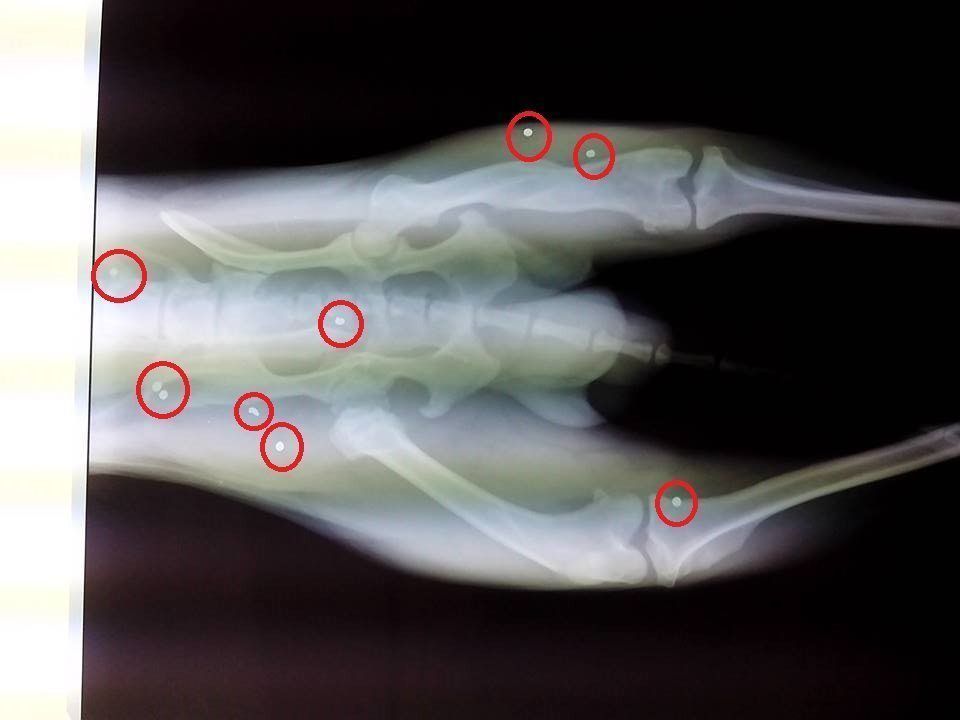

Με σπασμένα τα πίσω του πόδια, των οποίων τα οστά κόλλησαν μόνα τους στραβά, με δεμένο το ένα από τα άκρα του με σχοινί ή σύρμα, που έχει αφήσει ανεξίτηλο σημάδι στο σώμα του, αλλά και πυροβολημένο περιφερόταν στο χωριό Ράχη της Άρτας το σκυλί που βλέπετε στις φωτογραφίες.

RaxiArtasSkylos3Η ακτινογραφία έδειξε ότι και τα οστά των πίσω ποδιών του ζώου έχουν σπάσει και κολλήσει στραβά αλλά και τα σκάγια.

Είναι αδύνατον να γνωρίζουμε αν ο ίδιος δράστης αρχικά το έδεσε από το πόδι για να το βασανίσει, του έσπασε τα δύο πίσω άκρα και το πυροβόλησε ή αν αυτά τα γεγονότα συνέβησαν σε διαφορετικές χρονικές περιόδους. Σημασία έχει ότι το ζώο που είναι πολύ φιλικό με τους ανθρώπους – αλλά δυστυχώς γι’ αυτό κυνηγάει τα μηχανάκια – έχει πέσει θύμα σαδιστών κατοίκων της Ράχης οι οποίοι θέλησαν να το εξοντώσουν με κάθε τρόπο.

Το ζώο εμβολιάστηκε και αφού διαπιστώθηκε ότι μπορεί και κινείται φυσιολογικά έστω και με τα τρία πόδια – καθώς αυτό που ήταν δεμένο με σχοινί ή σύρμα πλέον δεν το πατάει καθώς τα οστά έχουν δέσει στραβά – χωρίς να πονάει μεταφέρθηκε ξανά και στη Ράχη της Άρτας.